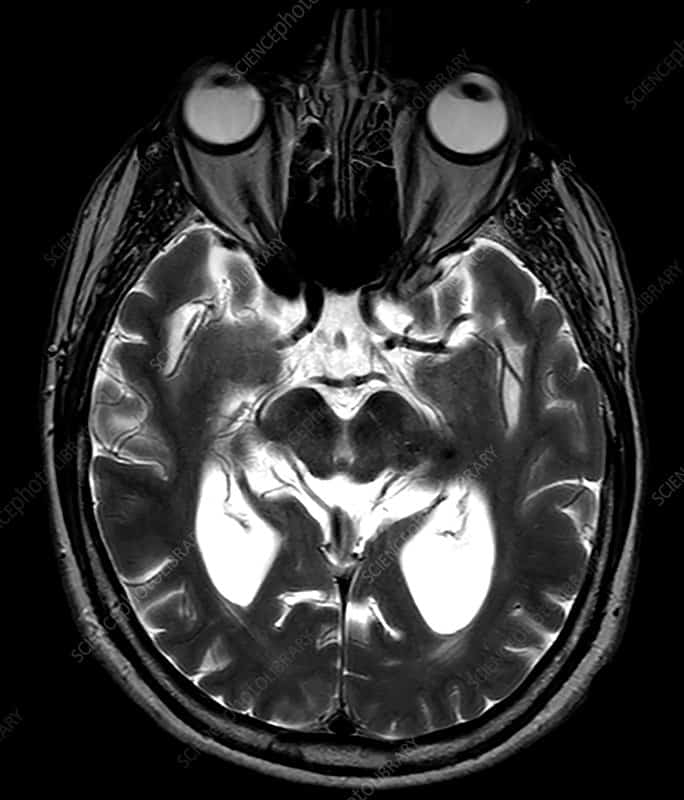

- अगर ऐसा है, तो डॉक्टर MRI टेस्ट की सलाह दे सकते हैं, ताकि वो जान पाएं कि क्या आपके प्रोग्रेसिव सुपरान्यूक्लियर पाल्सी से जुड़े मस्तिष्क के कुछ खास भागों में सिकुड़न है या नहीं। MRI से उन विकारों के बारे में पता चल सकता है जो प्रोग्रेसिव सुपरान्यूक्लियर पाल्सी की तरह लग सकते हैं, जैसे की स्ट्रोक।

- पॉज़िट्रान एमिशन टोमोग्राफी (PET) स्कैन की सहायता से दिमाग में बदलाव के शुरुआती लक्षणों का पता चल सकता है, जिनका MRI से पता नहीं चलता।